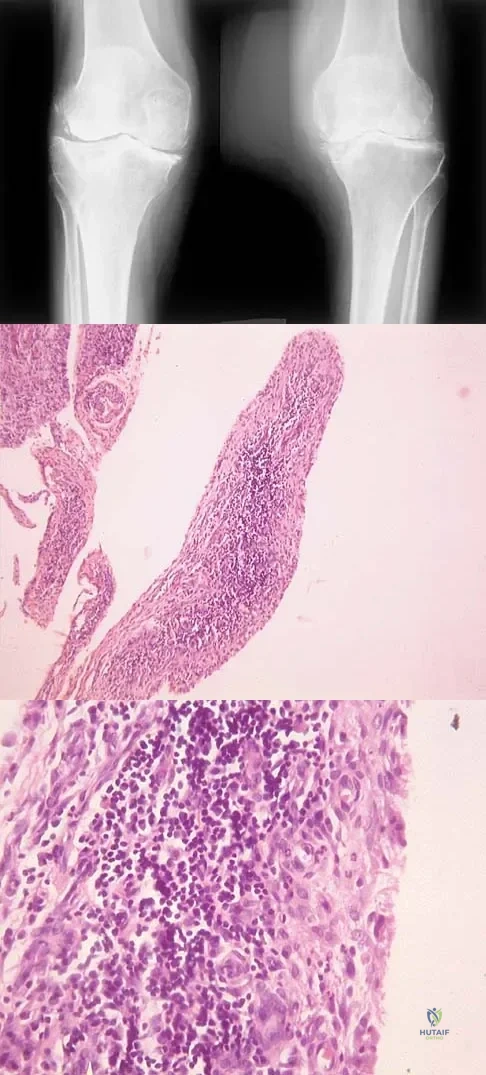

Question 24

A 10-year-old boy has had wrist pain for the past 3 months. He denies any history of trauma. He reports mild tenderness associated with a palpable mass. A radiograph and biopsy specimens are shown in Figures 52a through 52c. What is the most likely diagnosis?

Explanation